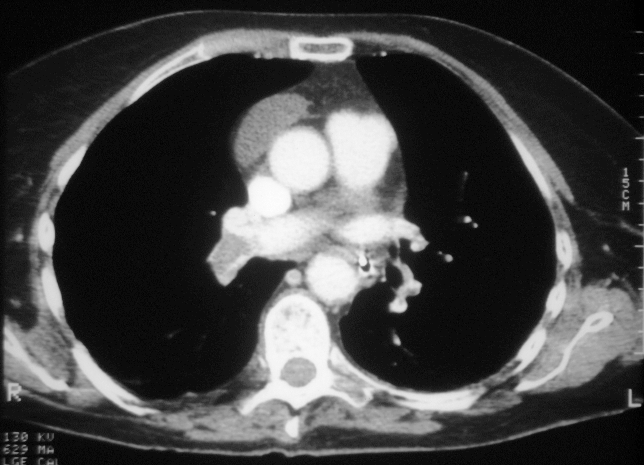

Cóagulos observados por Tomografía Computarizada